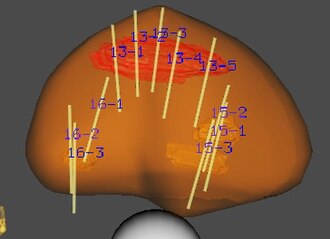

Brain FDG-PET phantom showing cortical glucose metabolism pattern, useful for Alzheimer's disease and epilepsy evaluation